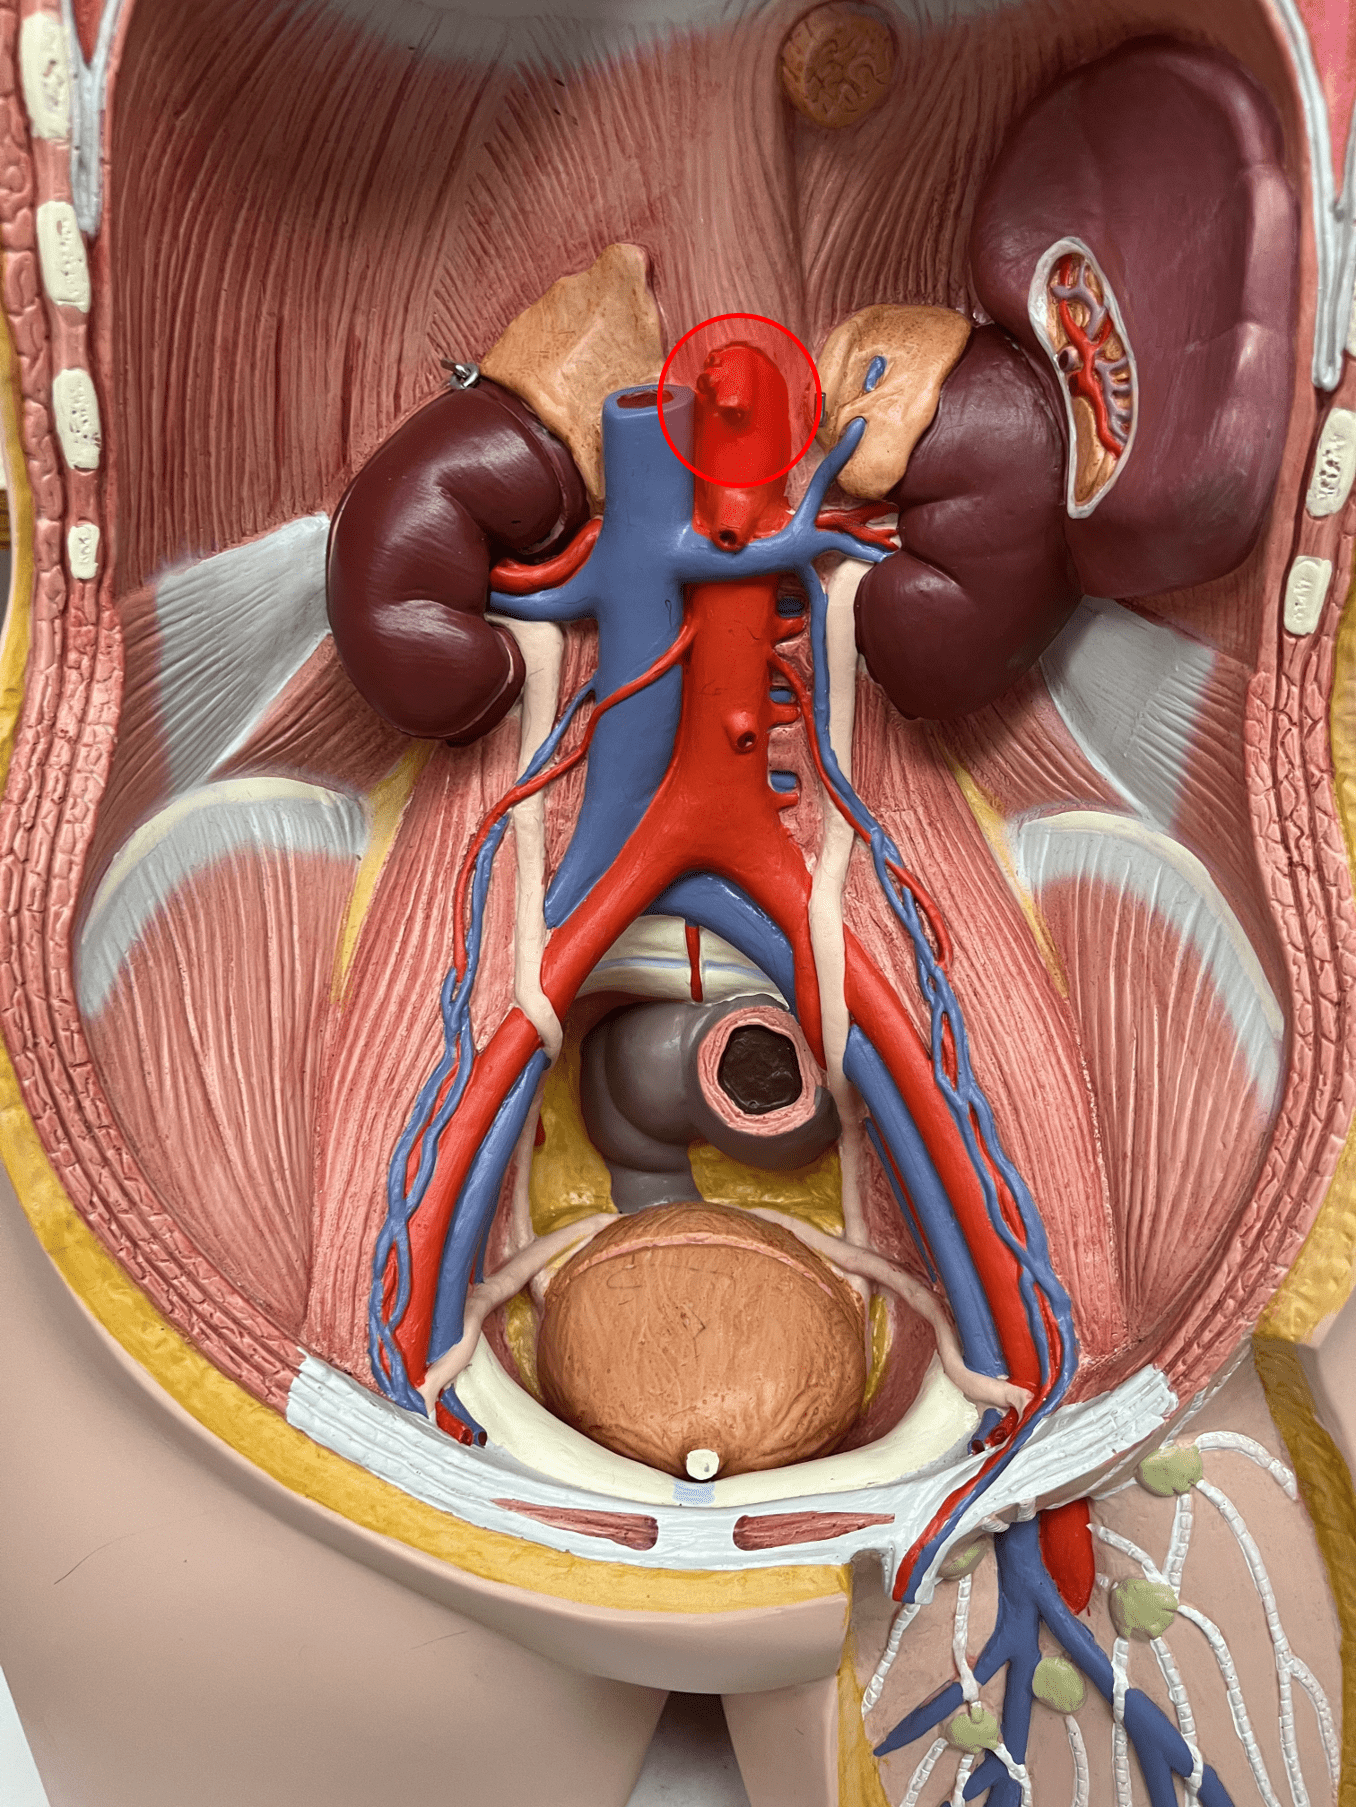

tunica externa

• Composed of loose connective tissue and collagen fibers.

• Also known as the tunica adventitia.

7

New cards

external elastic membrane

• A thin layer of elastic connective tissue.

• Found between the tunica externa and tunica media.

• Found between the tunica externa and tunica media.